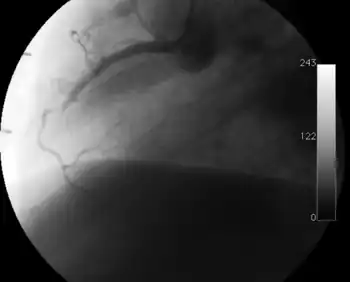

Coronary angiography

Surveillance is performed by regularly repeating coronary angiography in the cardiac catheterization laboratory, the diagnostic test of choice.[2] This is typically performed annually for the first five years after transplantation.[8] Angiography in CAV characteristically demonstrates diffuse stenoses in large coronary arteries and a reduced number of smaller coronary arteries, also known as "peripheral pruning".[2][6] However, because CAV frequently affects the entire length of the coronary artery, CAV may not be apparent by angiography alone.[2]

Occlusion of the right coronary artery 2 years after heart transplantation.